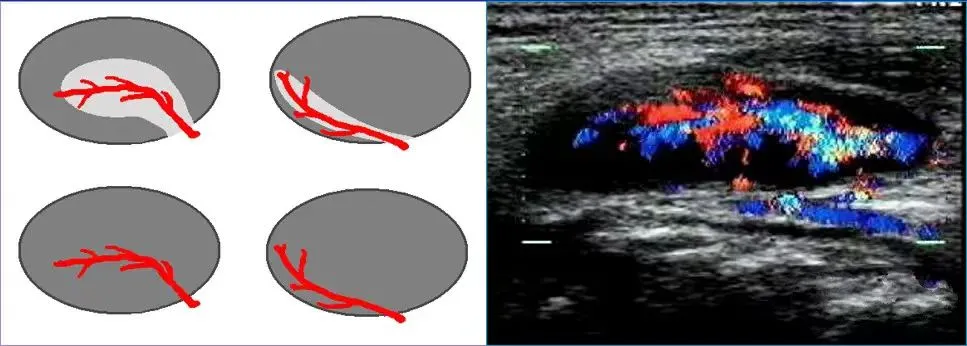

淋巴门型

血流信号沿着高回声的淋巴门分布,或从淋巴门血管主干放射状发出,该血流可位于淋巴结中央或边缘,多见于良性淋巴结及淋巴瘤。

中央型

血流信号位于淋巴结中央,经多切面扫查均显示该血流信号不是来自淋巴结门部,尤其是紊乱的中央型血管见于恶性淋巴结。

周边型

血流信号位于淋巴结周边部,而淋巴门无血流信号,多见于淋巴结转移癌和淋巴瘤。

混合型

同时显示上述三种血流类型的两种或三种,可见于恶性淋巴结和结核性淋巴结。